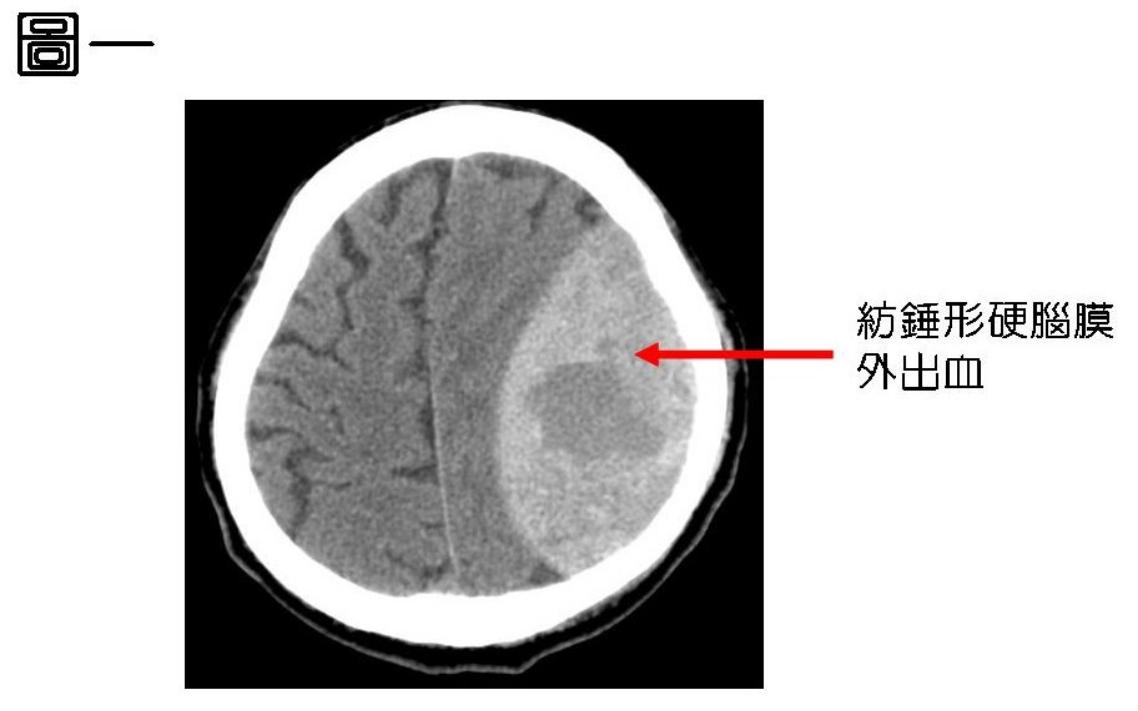

張啟文也提到,硬腦膜外出血的症狀和出血的位置及出血量有關係,可以是沒有明顯症狀,或是頭痛、嘔吐,或一側癱瘓,更嚴重 的是意識不清、昏迷,甚至死亡。而硬腦膜外出血的診斷主要是透過頭部的電腦斷層掃描(CT),紡錘型的高密度區塊就是硬腦膜外出血,如(圖一)。